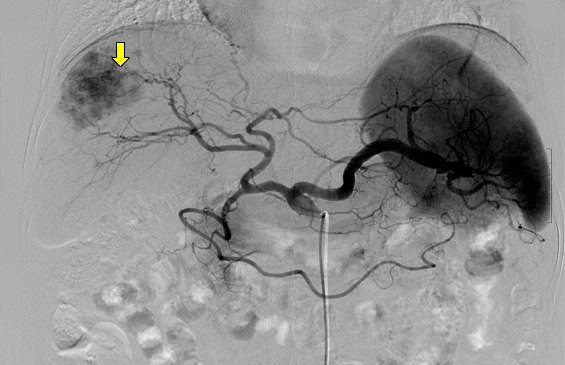

혈관조영검사에서 나타난 간암

서혜부(사타구니)에 위치한 대퇴동맥을 통하여 카테터(catheter)라고 하는 약 2~3mm 정도의 가는 관을 삽입하여 간동맥으로 접근한다. 카테터가 간동맥에 들어가면 혈관조영제를 주사하면서 간동맥 조영 사진을 얻어 종양의 위치, 크기 및 혈액 공급 양상 등 치료에 필요한 정보를 얻는다. 치료 방침이 정해지면 종양으로 가는 간동맥을 찾아 항암제와 색전 물질을 (혈관을 막는 물질) 주입한다.